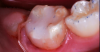

A 9-year-old boy had a partially erupted mandibular first molar with much hypocalcification of the occlusal surface and a large caries lesion involving the occlusal and buccal surfaces (Figure 1). The patient complained of continuing sensitivity to cold stimulus and air inspiration. Because the tooth was only partially erupted, consideration for stainless steel crown full coverage had to be delayed. As an interim repair, it was decided to debride the carious tooth substance and place a light-hardened calcium silicate/mineral trioxide aggregate (MTA) liner, followed by a bonded restoration. After inferior alveolar block anesthetic injection and cotton roll isolation, cavity outline form was cut using a high-speed, water-cooled, medium-grit cylindrical diamond bur (Figure 2). Insufficient eruption precluded use of a rubber dam. A large, round bur at slow speed was used to debride the carious enamel and dentin. The prepared surfaces were swabbed for two 60-second applications of a 5% glutaraldehyde/HEMA solution for desensitization and disinfection of the preparation.6,7 Cavity liner was then injected and spread over the deepest sections of the cavity floor and hardened with the visible light beam (Figure 3). After a self-etching bonding agent was applied over the remaining enamel surfaces, without the need for any type of matrix, an RMGI bioactive ionic resin-based composite was injected, in one portion, into the preparation and spread over the four cusps using a ball burnisher. This restorative complex was then photo-polymerized using two 20-second exposures of the visible light beam (1,200 mW/cm2). The restoration was trimmed and finished with large, round diamond burs at slow speed, and occlusion was evaluated with articulating paper and adjusted.

Cavity liner was placed and light-hardened.

Figure 3

Images of the repaired molar immediately after restoration

Figure 4

13 months postoperatively

Figure 5